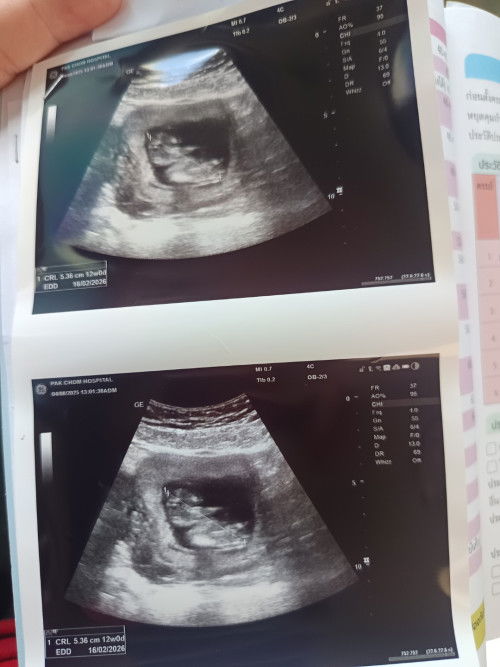

12weekค่ะ# ทีมมีนา😊

ทีมเดียวกันเลยค่ะ 12วีค4วันนมีนาคม💖